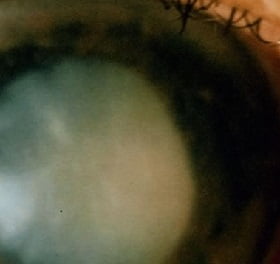

- катаракта;

Самая распространенная форма глаукомы — открытоугольная. Очень часто протекает практически незаметно для больного. Глаз выглядит нормально, но водянистая влага, не имея нормального оттока, скапливается в глазу, что приводит к повышению внутриглазного давления. И это, может быть, самая неприятная особенность открытоугольной формы — болезнь прогрессирует незаметно, а ведь без лечения глаукома рано или поздно приводит к полной потере зрения.